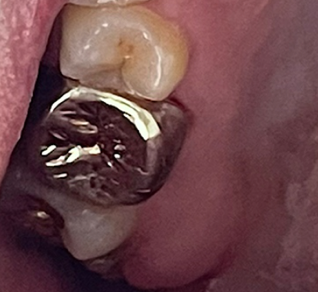

저는 치석이 주로 앞니 안쪽 편에 많이 있었는데요. 제 치석 사진입니다. (혐 주의)

병원에서 편안하게 스케일링을 해 주셔서 치석을 제거할 수 있었습니다.

아쉽게도 치석 떨어지고 나서 사진을 안 찍었었네요. 무슨 금속 덩어린 줄 알았었습니다 ^^;

큰 덩어리가 떨어지고 나니 치석 빠진 부분이 허전해서 한동안 뭔가 되게 허전한 느낌이었습니다. 그리고 잇몸이 올라오기 전까지는 구멍이 나 있었는데 다행히도 잇몸이 올라와서 메워지더군요.